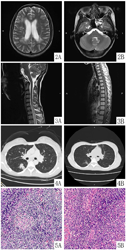

颅脑及脊髓MRI可见多发病灶(图2、图3);胸部CT提示右下肺炎症(图4);2021年7月12日脑脊液常规、生化未见明显异常,脑脊液中枢神经系统副肿瘤抗体、中枢神经系统脱髓鞘抗体、霍奇金淋巴瘤相关性脑炎抗体未见异常;血清、脑脊液寡克隆带(+),血清中枢神经系统脱髓鞘抗体、霍奇金淋巴瘤相关性脑炎抗体未见异常;2021年7月22日全身PET/CT:(1)脾大,糖代谢未见明显增高;全身多发骨髓糖代谢弥漫性增高;(2)全身多发小淋巴结,部分淋巴结周围脂肪密度增高,糖代谢未见异常,考虑反应性增生或者其他良性病变。

2021年7月7日"右颈部淋巴结活检":淋巴结反应性增生,以T淋巴细胞增生明显伴EBV感染(图5)。